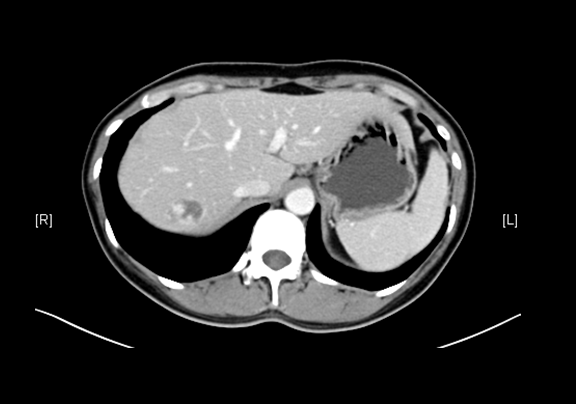

上腹部增强CT示:肝右叶海绵状血管瘤可能性大;肝囊肿;左肾上极肿瘤可能性大;双肾多发囊肿。

术前CT检查:

动脉期

静脉期

平衡期